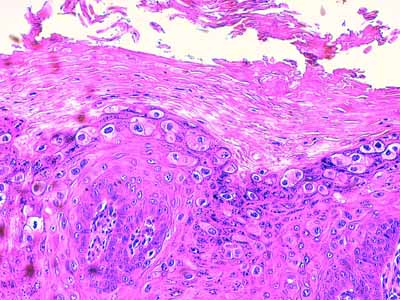

A l’examen histologique, on observe des néoformations verruqueuses, exophytiques, constituées d’un épiderme bien différencié, sévèrement hyperplasique, produisant à la surface du tégument, des projections digitées, longues et étroites (Fig 2). Cet épiderme est le siège d’une sévère hyperkératose orthokératosique ou parakératosique et d’une hypergranulose avec de volumineux grains de kératohyaline (Fig 3 &6). Sa couche basale est très développée, cellulaire, mitotique, hyperbasophile (Fig 4 & 5). Les acanthocytes sous-cornés sont vacuolisés (Fig 3 & 7). Ils montrent un cytoplasme bleuté, discrètement fibrillaire (Fig 6), ou vacuolisé, leur noyau parfois pycnotique étant entouré d’un halo clair. Il s’agit de koïlocytes (Fig 7). Certains montrent un noyau avec margination chromatinienne laissant un centre bleuté compatible avec une inclusion basophile (Fig 7). Dans le derme papillaire sous-jacent, on observe un infiltrat inflammatoire lympho-plasmocytaire d’intensité modérée. Absence d’image suspecte de malignité.

Photo 2 (Hémalun Eosine X 100) : L’épiderme exprime une hyperplasie papillomateuse,

produisant à la surface du tégument, des projections digitées, longues et étroites,

parfois ramifiées (papilles). Cet épiderme est le siège d’une sévère

hyperkératose orthokératosique.